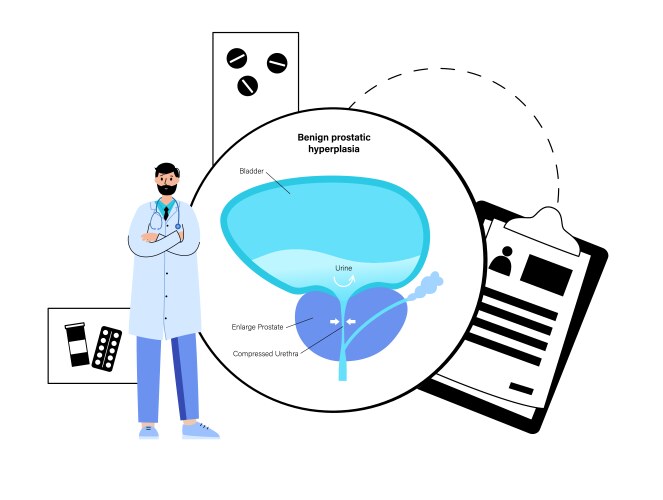

- Bph

- Prostate

- Treatment

- Enlarged

- Anatomy

- Bladder

- Cancer

- Disease

- Doctor

- Prostatitis

- Tumor

- Urology